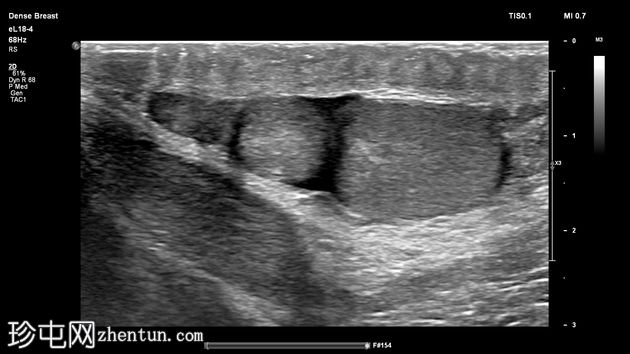

左侧阴囊内可见两个相邻但彼此分离的小睾丸,头侧体积分别为1毫升和3.5毫升,共用一个附睾。

两个睾丸回声和血流均正常,内部未见病变,但患侧可见少量鞘膜积液。